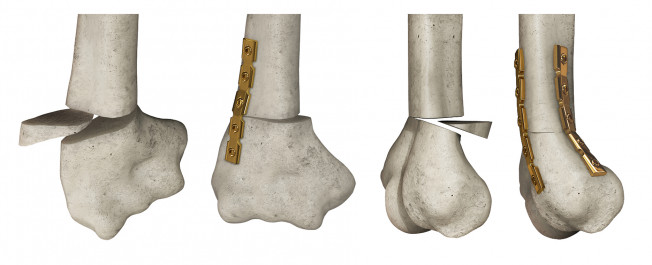

홍보, 학회 발표, 수술 교육, 의학 제품 소개와 관련한 영상을 3D로 제작하여 제공해드립니다.

제작범위 : 신체 전신, 뼈대, 장기, 혈관 등 사람, 동물의 모든 표현이 가능하며, 수술과 관련한 도구 제작도 가능합니다.

-이동훈연세정형외과 - 엑스다리, 오다리 등 다양한 수술 영상 제작